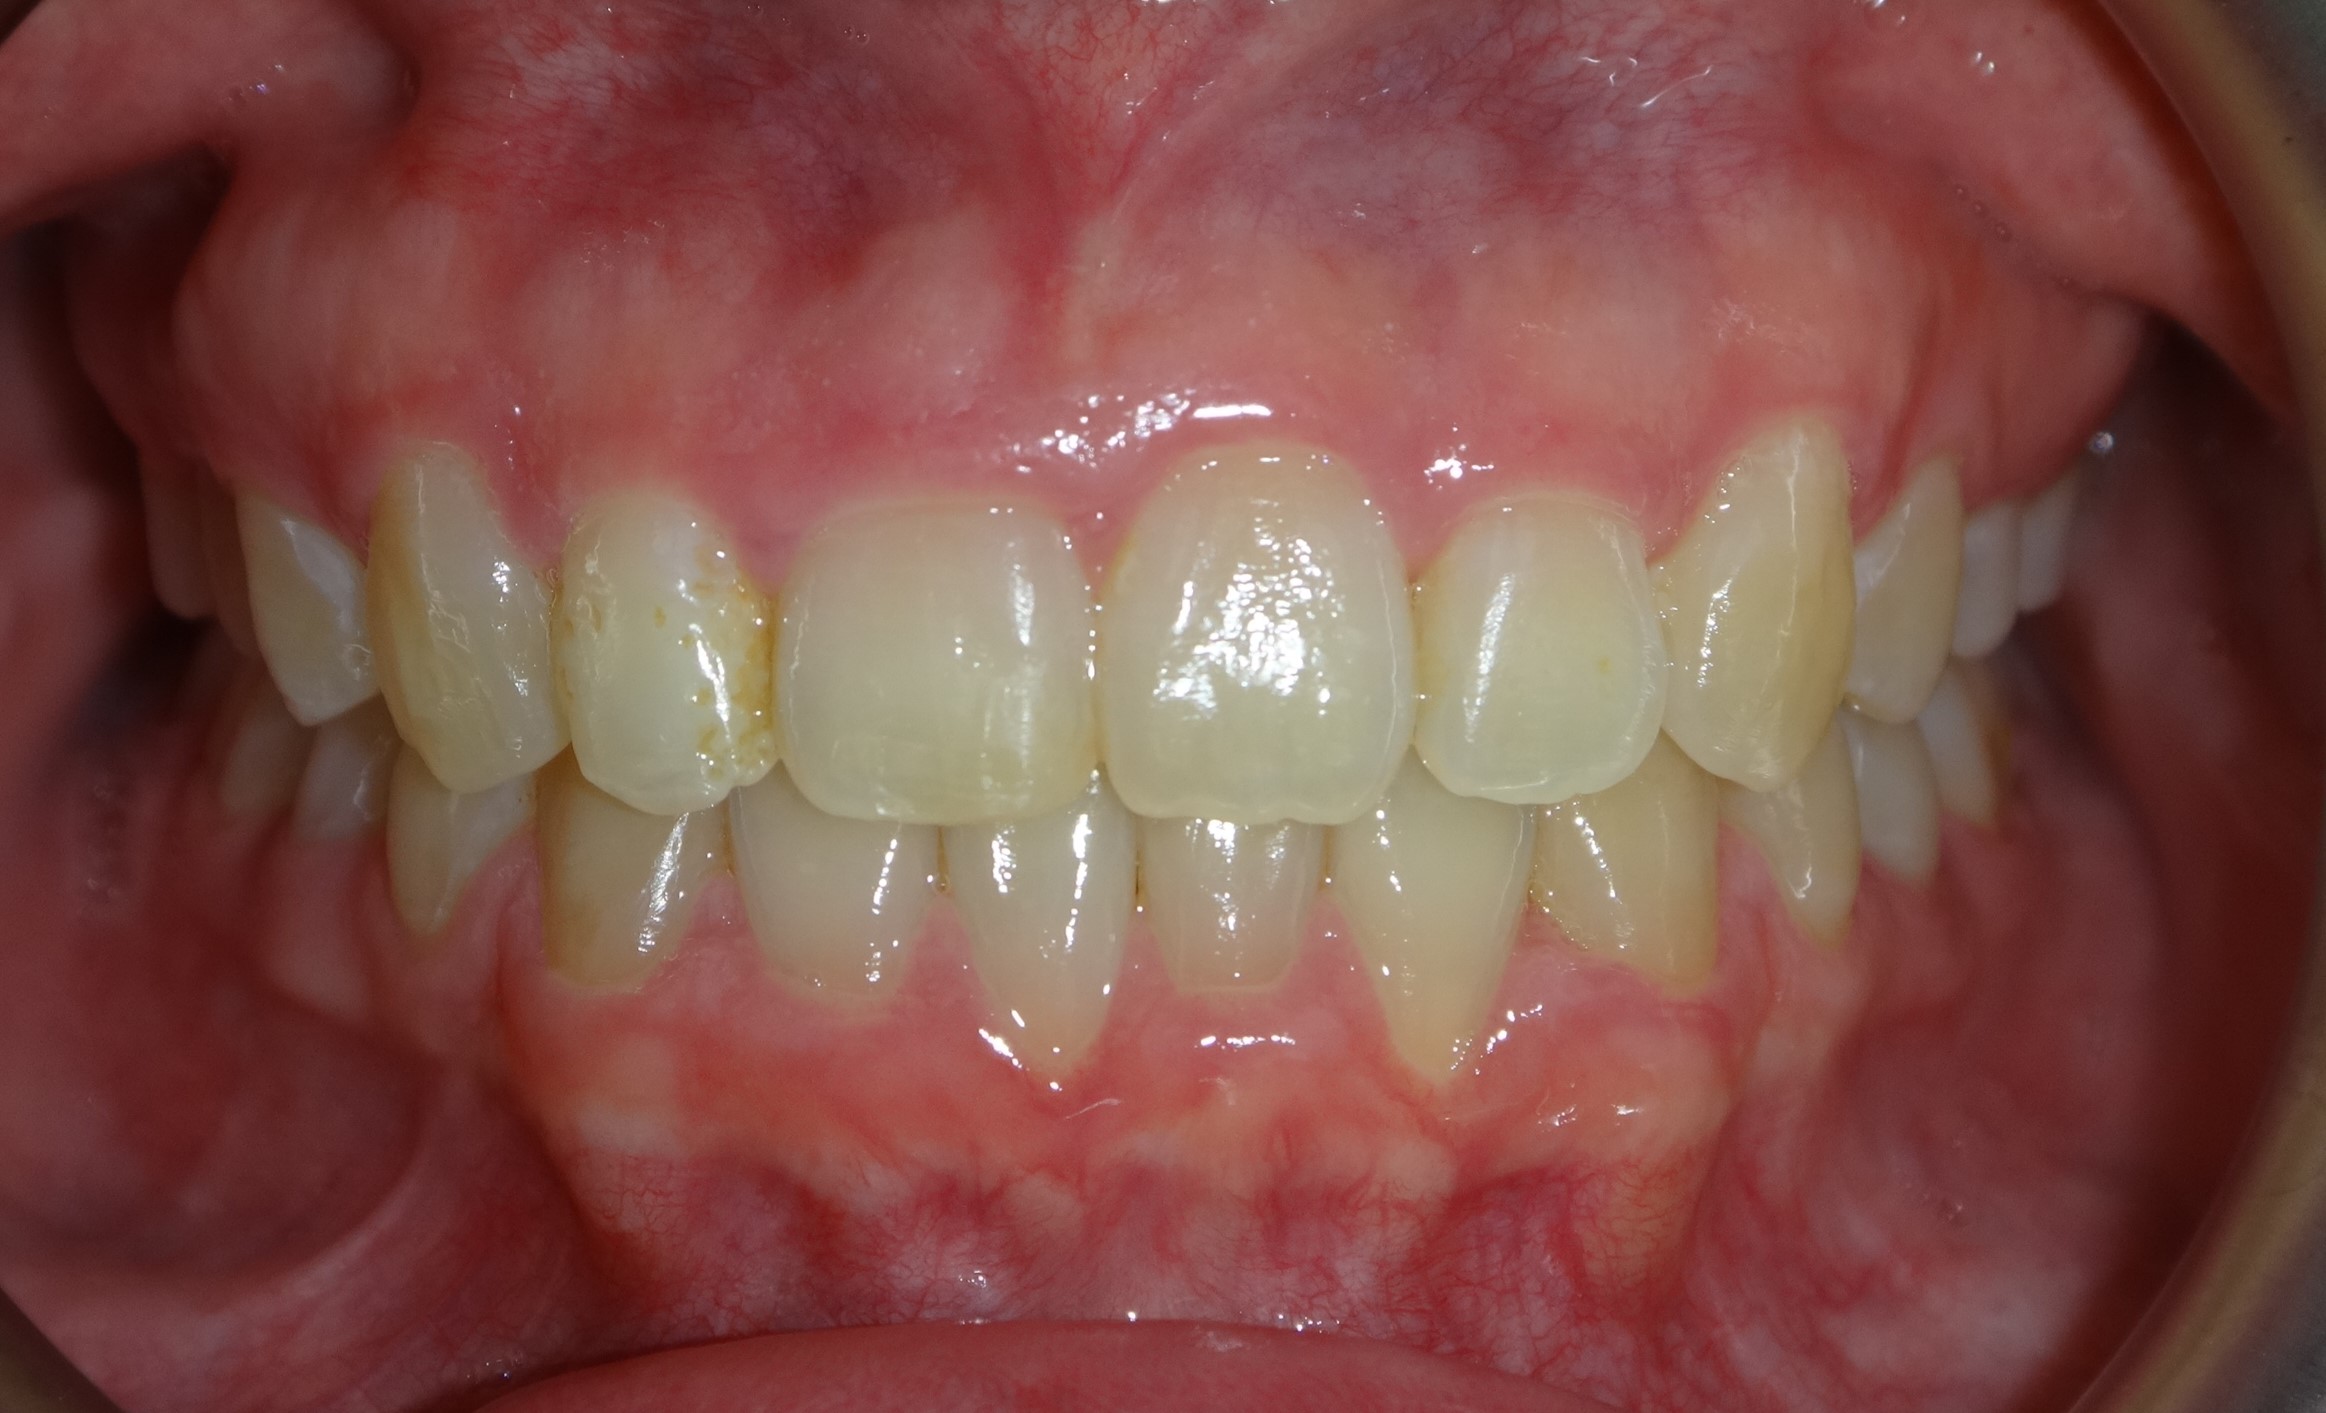

不拔牙案例 首頁 案例分享 齒顎矯正 不拔牙案例 - 矯正不拔牙案例 - 年紀:27歲 治療方式:隱適美隱形矯正 時間:34個月 主訴:前牙錯咬、排列不整 矯正前 矯正後 矯正前 矯正後 矯正前 矯正後 聲明:本所療程皆由專業醫生評估後,依照個人口腔狀況進行治療。因每位患者個別狀況不同,術後狀況也不盡相同,需親來本所由醫生評估。